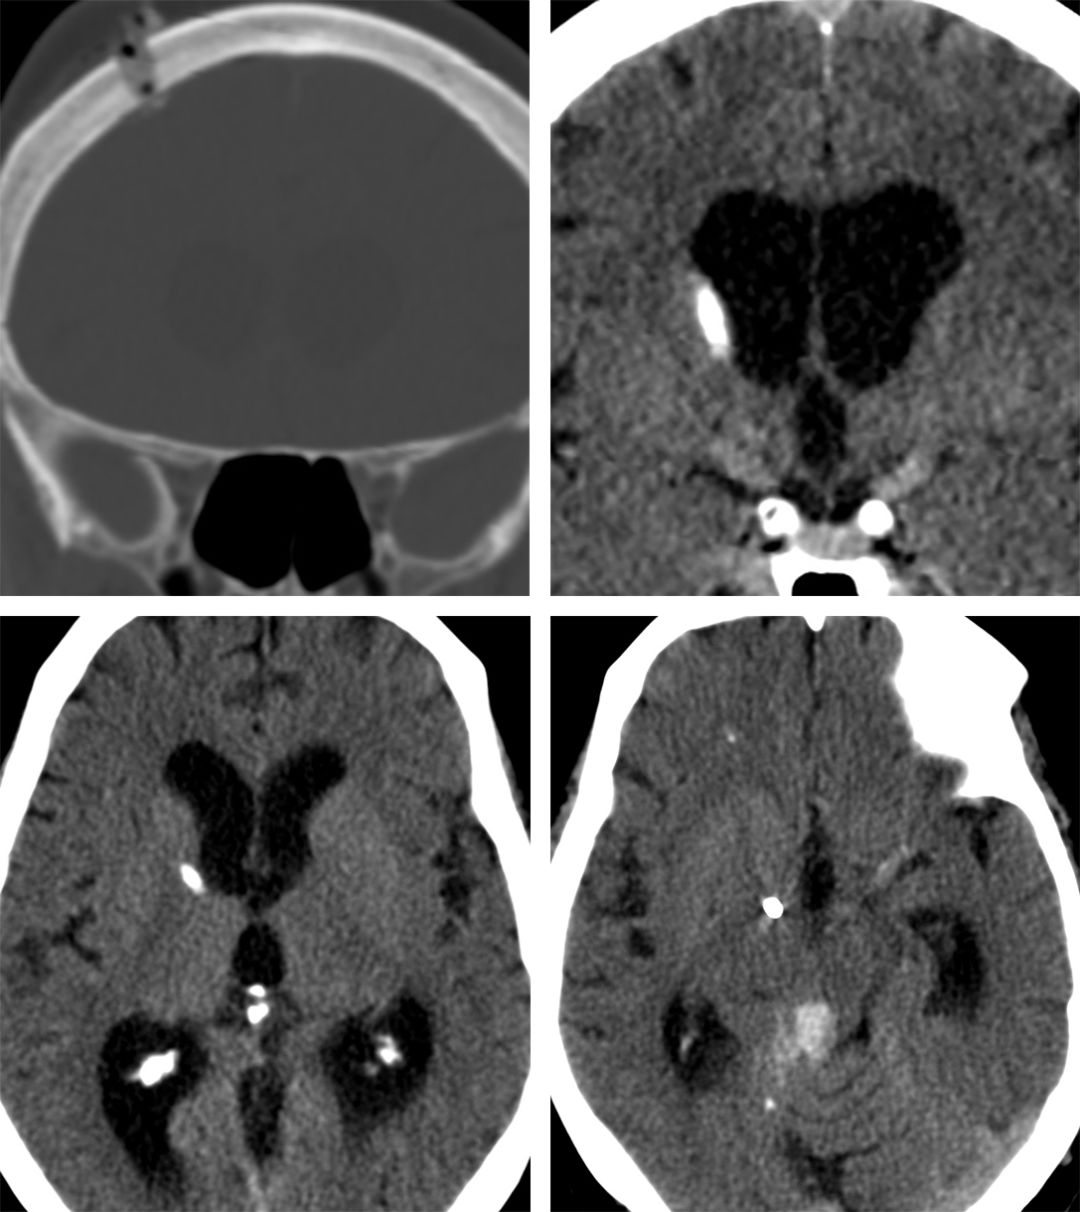

下面是一个由于开颅口过小导致EVD导管位置错误的例子。

图9. 这个EVD导管可能只是因为小孔的内边缘导致轻微偏移(左上冠状位CT)。导管刚刚好偏出侧脑室(右上图)。由于未进入脑室,术者将导管插入大于允许的深,导管尖端位置过深(下列)。